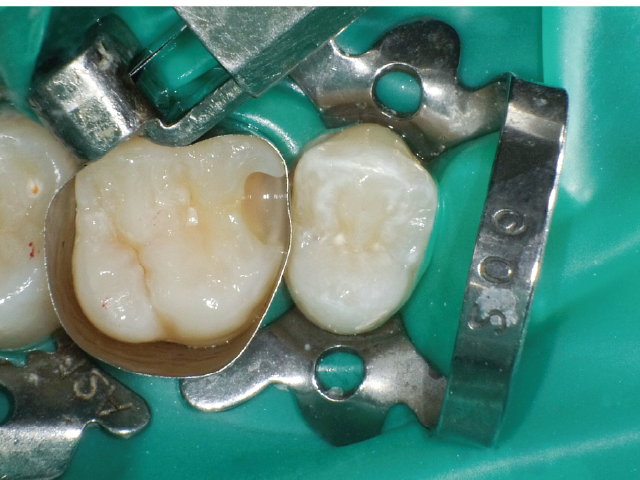

①窩洞形成段階(図1~7)

本症例では、ダイヤモンドの微粒子でコーティングされたエアースケーラーチップを窩洞形態の仕上げに使用。隣在歯の誤切削を防止し、エナメル質の切削断面を歯肉側窩縁までなめらかになるよう仕上げました。

②充填段階(図10~22)

窩洞形成完了後は隣接面部健全歯質の残存範囲によりコンポジットレジンの充填時に用いるマトリックスシステムを選択していきますが、今回はシンプルな操作で設置可能なトッフルマイヤータイプのマトリックスシステムを選びました。隣在歯との距離が小さく、フラットな隣接面形態の再現が必要な症例には最適で、同時に精度の高い窩洞の防湿も可能です。使用したメタルのマトリックスバンドの厚さは30µmと非常に薄く、隣在歯との間に適切な接触関係を回復することができます。